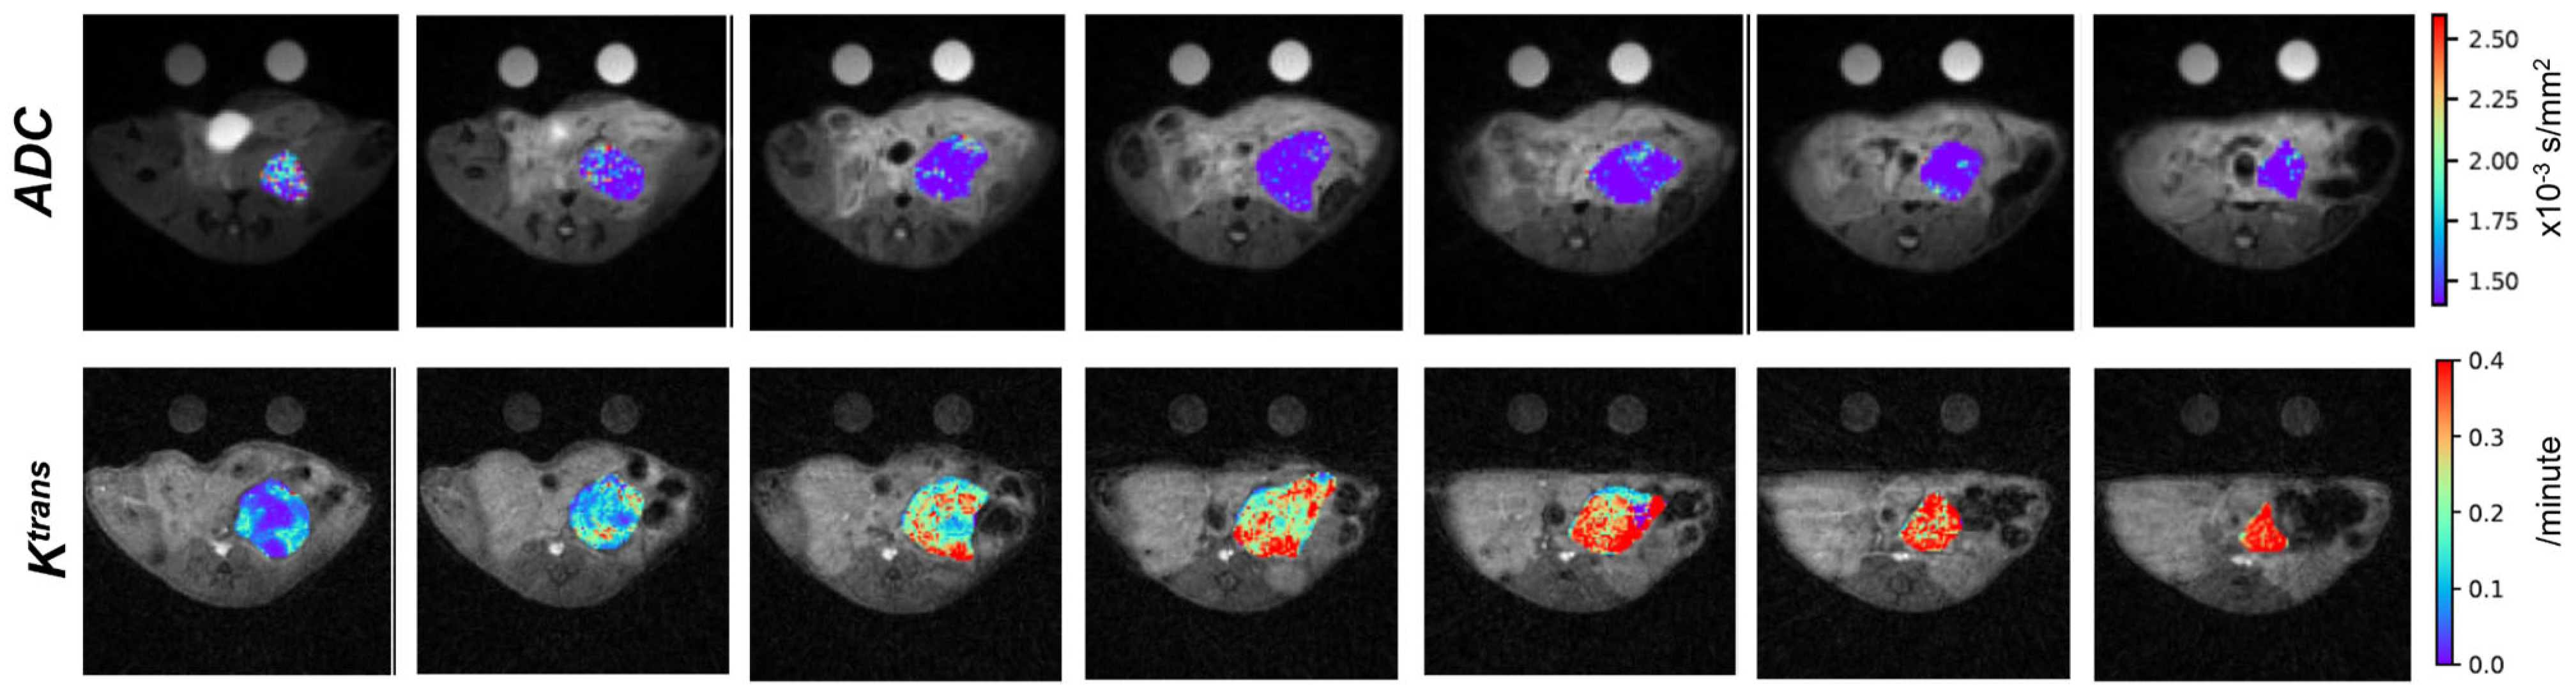

- Robison, T.H.; Solipuram, M.; Heist, K.; Amouzandeh, G.; Lee, W.Y.; Humphries, B.A.; Buschhaus, J.M.; Bevoor, A.; Zhang, A.; Luker, K.E.; et al. Multiparametric MRI to Quantify Disease and Treatment Response in Mice with Myeloproliferative Neoplasms. JCI Insight 2022, 7, e161457. [Google Scholar] [CrossRef]